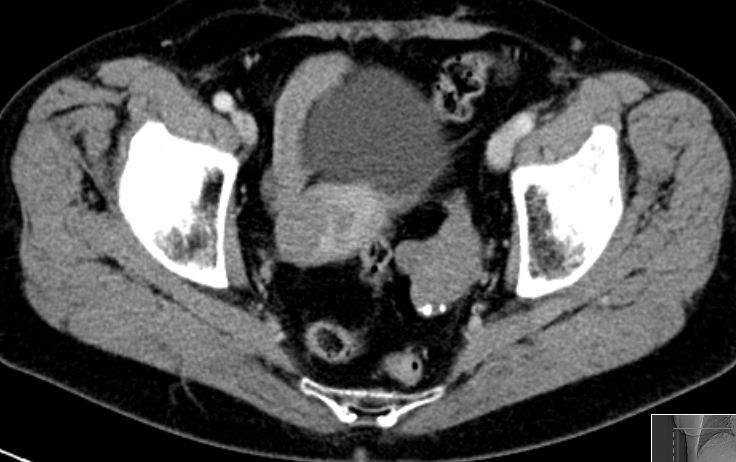

| Diagnostik | 70-jährige Frau mit einer RF des linken Adnex. Histologisch adulter Granulosazelltumor FIGO Ia.![]() |

| Morphologie | meistens unilaterale, solide (auch multizystisch) mit grauweißer oder gelblicher Schnittfläche. | |||